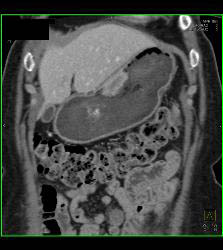

Bulky Tumor C/w Lymphoma Involving Stomach and Kidney